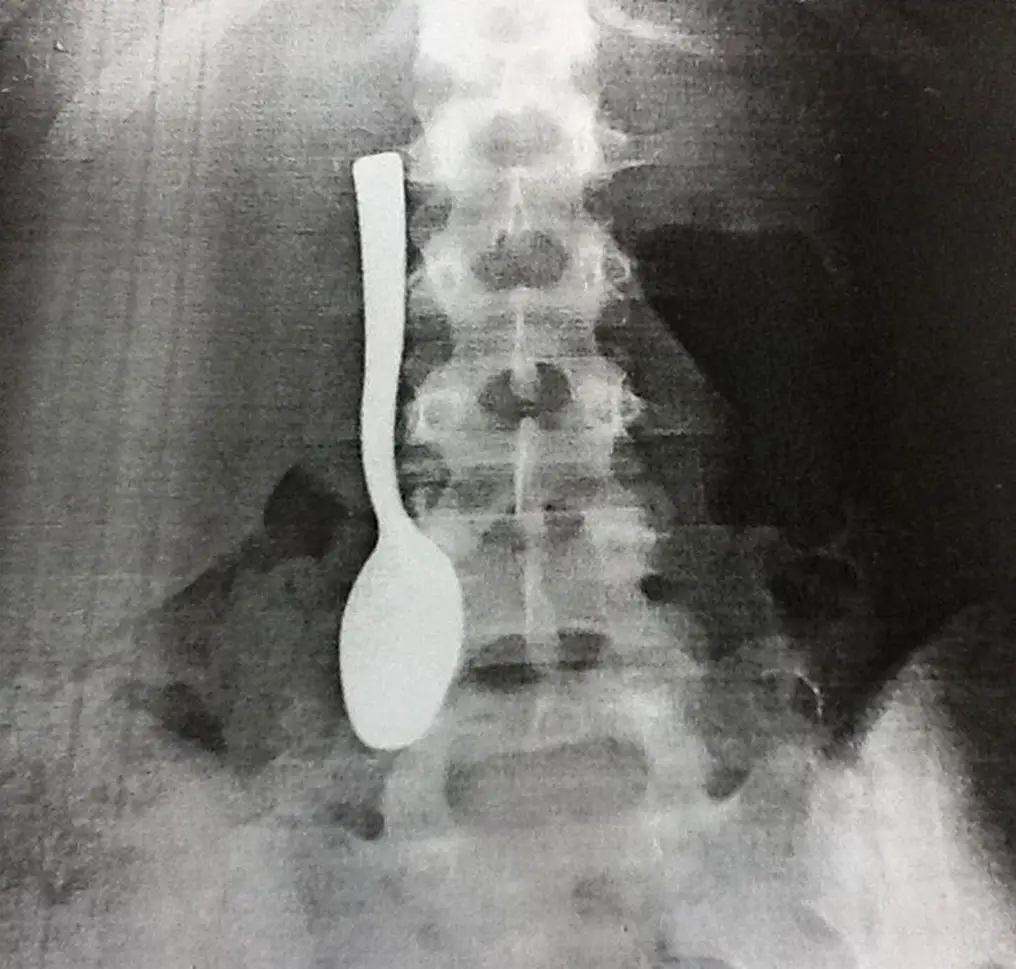

MEDICINA ONLINE OGGETTI CORPO ESTRENEO ANO BAMBINO ESOFAGO STOMACO BATTERIE SEX TOYS OGGETTI SESSO GIOCATTOLI TOSSICI BOTTIGLIA PENNA PENNARELLO COLON RETTO RISCHI COSA FARE COLONSCOPIA

Published 18/04/2018 at 1016 × 969 in Corpi estranei nel tratto digerente: rischi e cosa fare in bambini e adulti

MEDICINA ONLINE OGGETTI CORPO ESTRENEO ANO BAMBINO ESOFAGO STOMACO BATTERIE SEX TOYS OGGETTI SESSO GIOCATTOLI TOSSICI BOTTIGLIA PENNA PENNARELLO COLON RETTO RISCHI COSA FARE COLONSCOPIA INTESTINO DIGERENTE RX RADIOGRAFIA